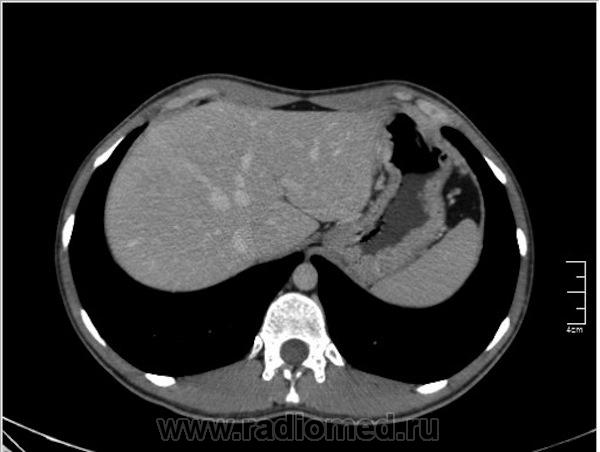

Уважаемые коллеги, особенно врачи КТ. Надеюсь что данная публикация окажется полезной для многих из Вас. Ниже представлены сканы печени; предлагаю Вам ознакомится с ними и высказать свое мнение. Пациент мужчина средних лет, специфичных жалоб не предъявляет.

Диффузное неравномерное утолщение стенок желудка - инфильтративное нео или лимфома... И еще похоже на пузырьки газа в стенке желудка. Если бы его (желудок) раздуть...

Нет, Вы не правы. Во первых нельзя адекватно судить о состоянии стенок желудка при отсутствии его контрастирования. В желудке гиподенсивное содержимое (жидкость), стенки спавшиеся, видны складки. Я написал в оглавлении, что публикую КТ именно ПЕЧЕНИ.

Ну, мне не нравится один маленький гиподенсный очажок в 8 сегменте.

На гемангиому похоже, контрастировать бы надо...

Евгений: В принципе похоже, весьма может быть. Тогда это простая инциденталома, т.е. находка не имеющая значения... А КТ с контрастом, обратите внимнаие на контрастированные гиперденсные печёночные вены.

Nela: Браво! Есть непрямые (вторичные) признаки объёмного образования печени (анатомия, анатомия и ещё раз анатомия!!!)

Уважаемый v1tal! Огромная Вам благодарность; Вы назвали ключевое слово: фаза! Высказанная Вами мысль, это моя основная цель данной публикации. Постараюсь позже более детально объяснить почему. Представленные сканы выше, были выполнены на стандартной портальное фазе. А сейчас, я покажу сканы данного пациента выполненные на артериальной фазе :

Да Ola la, Вы абсолютно правы; это Фокальная Нодулярная Гиперплазия печени (FNH Focal Nodular Hyperplasia). Одна из немногих гиперваскулярных опухолей печени. Наверное некоторые коллеги спросят, и зачем было изначально публиковать портальную фазу, на которой "не видно" (хотя опухоль видна, пусть и не напрямую, и Nela это доказала); и только потом показывать сканы на артериальной фазе, на которой всё "красиво и показательно". Постараюсь объяснить.